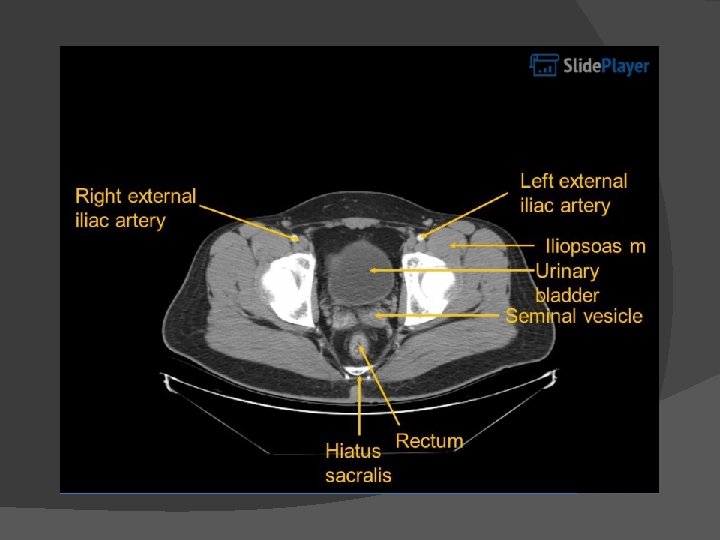

Abdominal CT